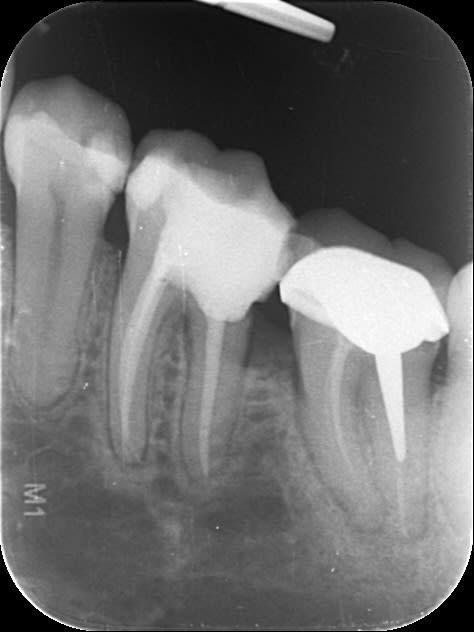

Et aujourd'hui, elle est contente plus aucune douleur sauf que en bouche je vois un bout d'os entre 35 et 36 et à la radio ... (image 3)

Outre le fait que je ne comprend pas trop ce que j'ai merdé, a votre avis c'est mort ou je tente de virer le fragment osseux de bien débrider et de voir ce qui se passe?

C’est le gros danger des intraligamentaires chez les fumeurs et aussi chez les diabétiques, nécrose osseuse due à un excès de vasoconstricteur sous pression.

Ca fait quand meme un gros morceau a enlever, c'est tout le septum qui a l'air de s'etre deplace vers le haut et qui donc serait mobile?

Tu as raison fatboy le morceau est important et je pense que la 5 et la 6 sont condamnées